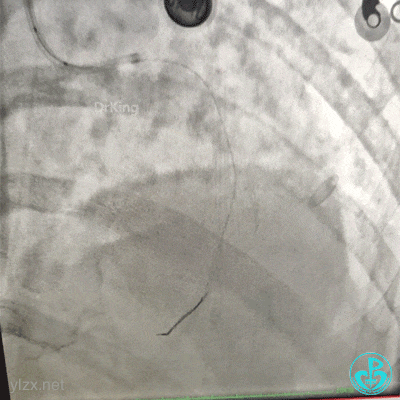

血压低,去甲肾上腺素8mg,25ml/h微量泵入,血压高时可维持在140/80mmHg左右,一直到手术结束。

2.0×15mm球囊预扩张后。

植入4.0×13mm支架1枚。